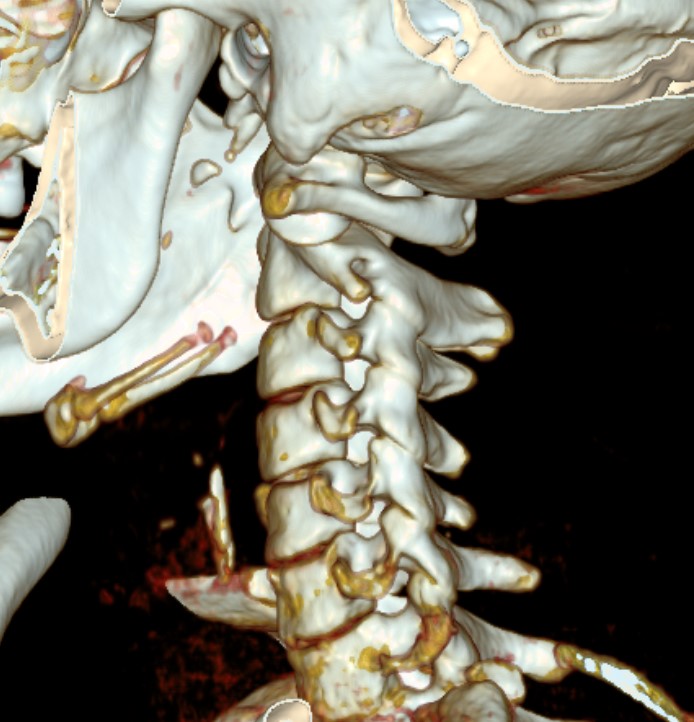

CT Scan

Atlanto-axial rotatory instability

Classification Fielding & Hawkins

| Type I |

Unilateral facet subluxation / dislocation ADI < 3 mm |

Transverse ligament intact | Most common |

| Type II |

Unilateral facet subluxation / dislocation Anterior displacement of the atlas by 3–5 mm ADI 3 - 5 mm |

Transverse ligament injury | |

| Type III |

Bilateral facet subluxation / dislocation Anterior displacement of atlas by more than 5 mm ADI > 5 mm |

Alar and tranverse ligament deficient Both lateral masses displaced anteriorly |

|

| Type IV | Posterior displacement of atlas | Ondontoid process deficient or fractured |

Rare Highest risk of neurological injury |